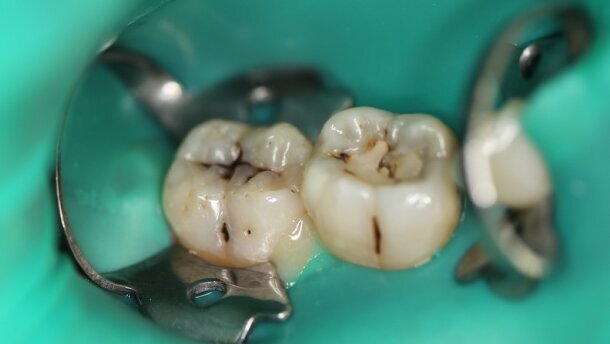

Do gabinetu zgłosiła się 23-letnia pacjentka, niepaląca, ogólnie zdrowa. W badaniu klinicznym stwierdzono: obecne ogniska próchnicowe w bruzdach policzkowych zębów 46 i 47, próchnica pierwotna na powierzchni żującej w zębie 47 i próchnica wtórna na powierzchni żującej w zębie 46. Pacjentka nie zgłasza dolegliwości bólowych ze strony tych zębów. Podczas preparacji zgodnie z koncepcją minimalnie inwazyjnej terapii, zastosowano różne techniki pracy laserem Er:YAG przy jednakowych parametrach (H14 conical tip, QSP, 0,90 W/90 mJ/10 Hz, 4 W/4 A).

Próchnicę średnią w bruździe policzkowej zęba 46 opracowano techniką bezkontaktową (głowica H02). Brak dolegliwości bólowych podczas opracowania (NRS=0). Próchnicę głęboka w bruździe policzkowej zęba 47 opracowano techniką kontaktową (głowica H14, końcówka cylindryczna). Umiarkowane odczucie bólu podczas opracowania (NRS=4). Próchnicę głęboką na powierzchni żującej zęba 47 opracowano metodą łączoną – turbiną (wiertło diamentowe) i laserem Er:YAG (głowica H14, końcówka cylindryczna). Podczas opracowywania wystąpiły silne dolegliwości bólowe (NRS=8), podano znieczulenie nasiękowe (Ubistesin forte ½ amp.) i zakończono preparację.

Wykonano bezpośrednią odbudowę tkanek twardych zębów materiałem złożonym (Gradia A3/NT).